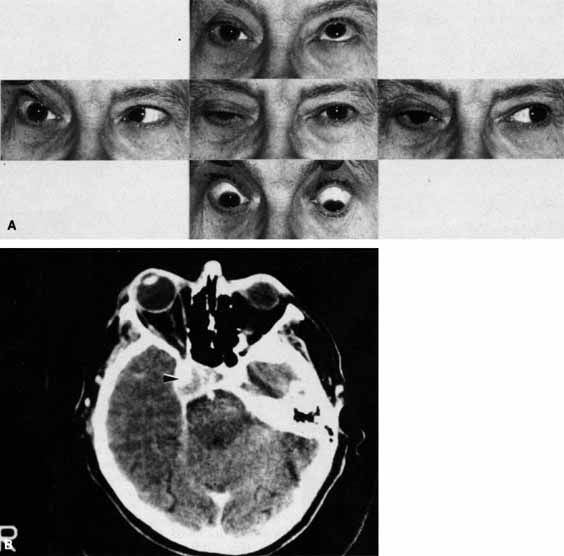

CASE 3

A 12-year-old child was referred by his school nurse because he had been complaining intermittently of double vision and the nurse had noted intermittent right ptosis. The child presented with a right ptosis and limited infraduction of the left eye (Fig. 24A). The ptosis worsened with prolonged up-gaze. A Cogan lid twitch was noted on the right with upward saccades. Injection of 1 mg of edrophonium resulted in complete resolution of diplopia and ptosis (Fig. 24B). The diagnosis was myasthenia gravis.

Fig. 24 A. A 12-year-old child presented with right ptosis and limited infraduction of the left eye. B. The ptosis resolved and eye movements were normal after injection of 1 mg of edrophonium. The diagnosis was myasthenia gravis.

Most orbital and cavernous sinus lesions produce afferent and efferent palsies in an anatomic pattern, for example, the superior orbital fissure has cranial nerves III, IV, VI and V1. When the pareses are not localized anatomically, or when there is variability in findings over time, one should include carcinomatosis or myasthenia gravis (see Fig. 24) in the differential diagnosis. Fatigability and a Cogan lid twitch strongly suggest myasthenia gravis.